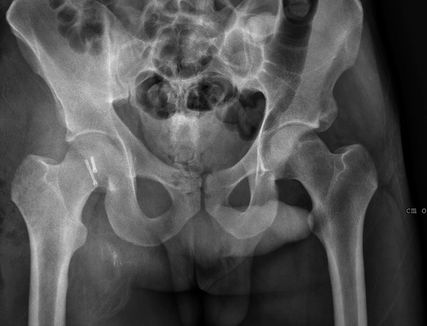

Abb. 3: Zur präoperativen Planung und zur Beurteilung des geschlossenen Repositionsergebnisses ist der Goldstandard die Computertomografie

Neben der klinischen Erstuntersuchung und Anamnese umfasst die Diagnostik die konventionelle native Röntgendiagnostik des verletzten Hüftgelenkes mit Standardaufnahmen im a.-p. und axialen Strahlengang (Abb. 1, 2) sowie gegebenenfalls die Anfertigung von Ala- und Obturatoraufnahmen. Obligatorisch empfehlen wir die Anfertigung eines Hüftübersichtsröntgens und gegebenenfalls, sofern möglich, auch eine Faux-Profil-Aufnahme. Zur präoperativen Planung und zur Beurteilung des Repositionsergebnisses ist der Goldstandard die Computertomografie (Abb. 3) mit Anfertigung einer 3D-Rekonstruktion. Im Rahmen der Notfalldiagnostik spielt die Magnetresonanz keine wesentliche Rolle. Im Hinblick auf die Diagnostik sekundär auftretender Komplikationen ist jedoch die Bedeutung des MRT unumstritten.